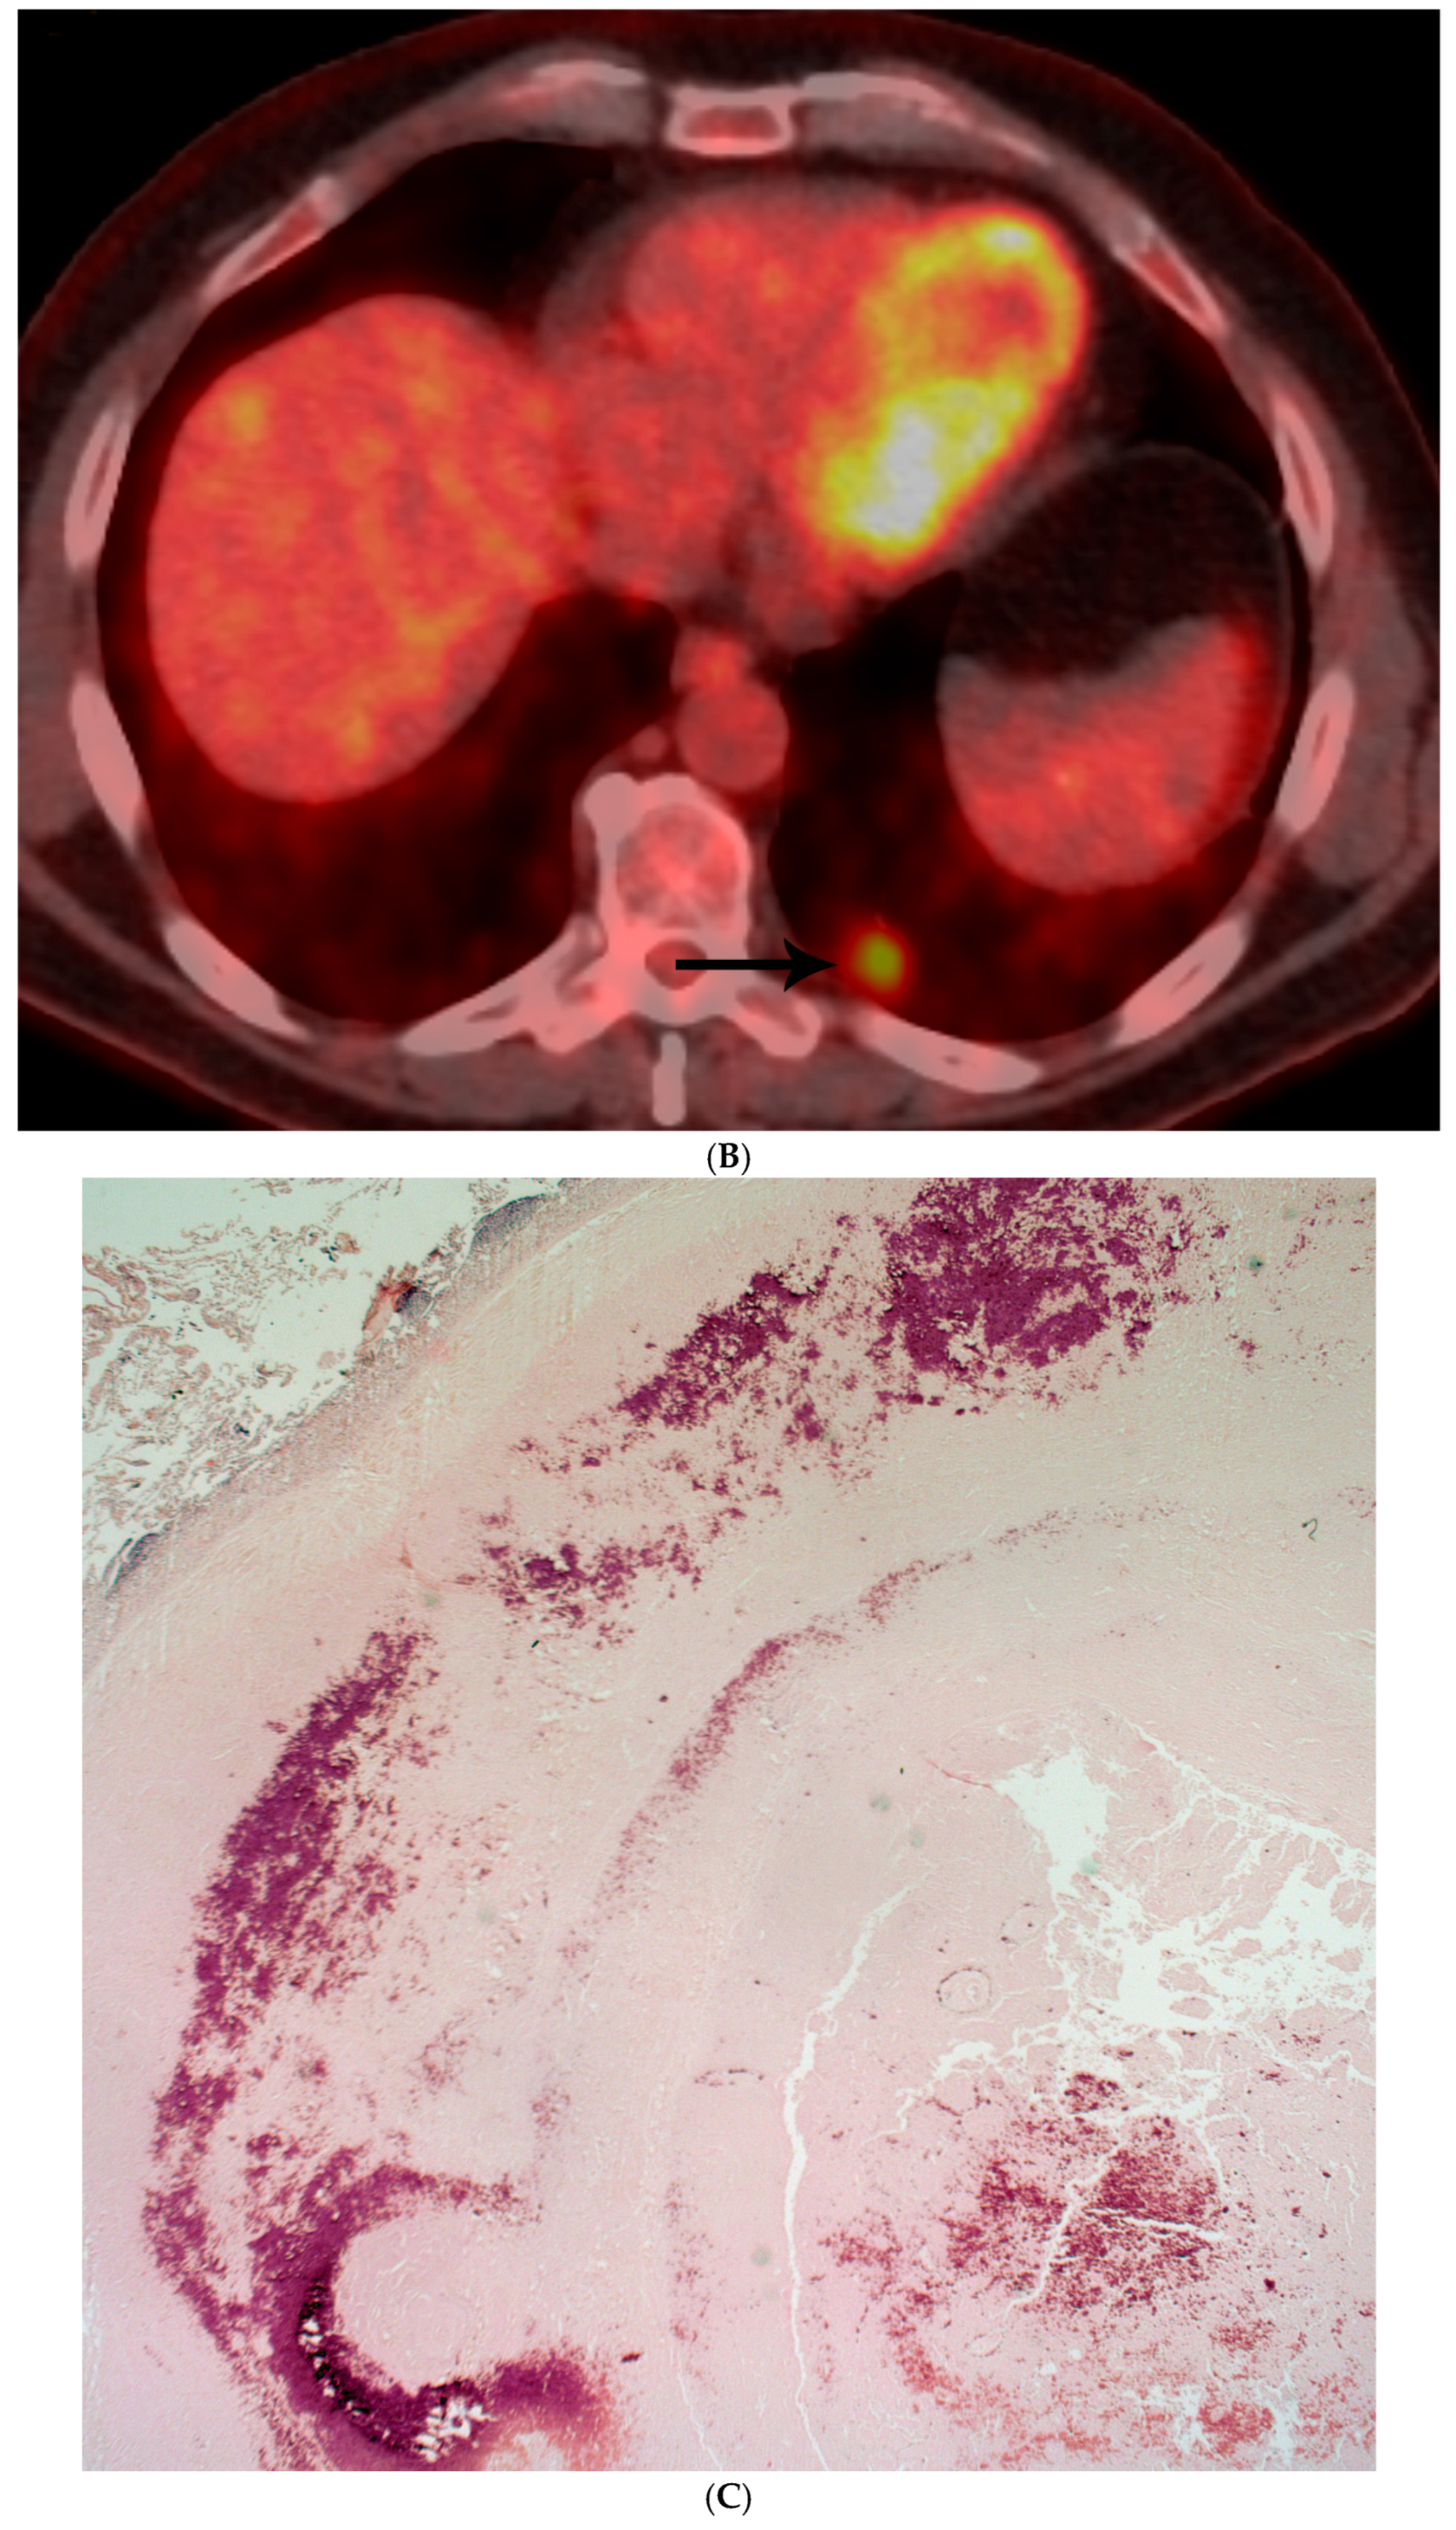

- Careful assessment of surgical material becomes highly important in identifying a fungal organism.

- Special histochemical stains (GMS) are recommended, and when needed, PCR studies are recommended.

- Morphological description of the fungal organism is an important role of the pathologist.